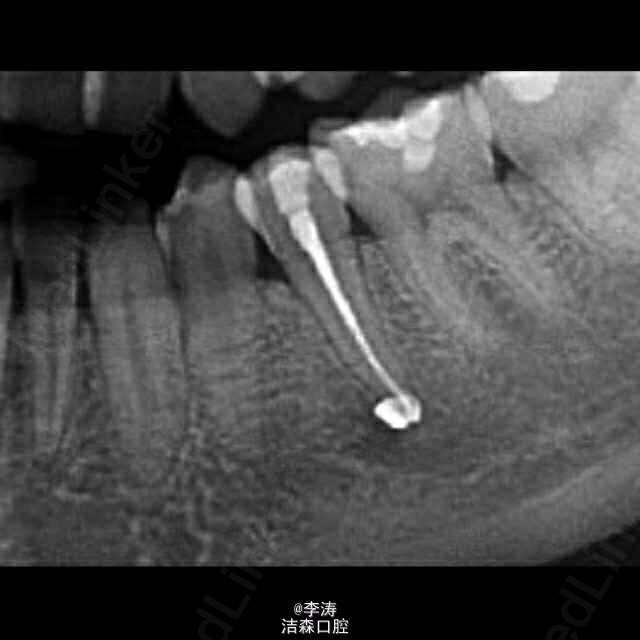

根管超填至颏孔一例,想要救你不容易!!!

遇一病人女性,20岁左右,两年前于外院35牙根管治疗,超充,正好超充于颏孔部位,患者现在还没有神经症状。该怎么补救?根尖手术,还是根管再治疗?或者有没有什么好办法?如果持续留在颏孔里面,久了会不会对神经产生什么影响?比如麻木???